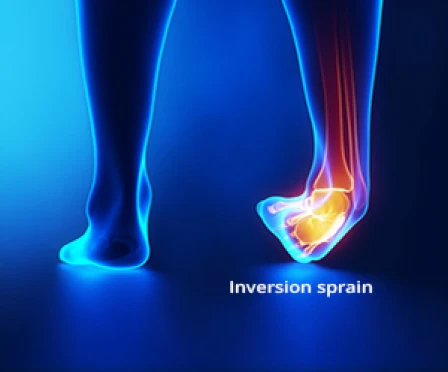

Ankle Sprains - Let’s talk about ankle sprains! A sprain is a partial or complete tear of a ligament and occurs when excess force is applied. The ligaments on the outside of the ankle are most commonly injured for two reasons: the lateral ligaments are weaker and they protect the ankle against rolling inward. We call this an “inversion injury” because the foot is moving in towards the midline of the body. Ankle sprains can also happen to the ligaments on the inside of the ankle, but occur with an “eversion injury”, or when the foot moves away from the midline. As some of you know first-hand, it is remarkably easy to roll your ankle! This can happen while landing from a lay-up in basketball, stepping in a hole outside, or even missing a step in your house.

Signs and symptoms of an ankle sprain include pain, swelling and bruising in the foot and ankle, and it is usually more painful when bearing weight on the affected side. Treatment is based on how badly the ligament is damaged but typically involves RICE - Rest, Ice, Elevation, and Compression. Sometimes crutches, ankle braces or physical therapy are needed to help with healing.